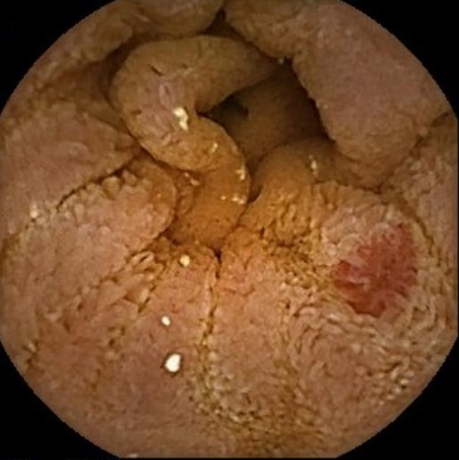

[Figure caption and citation for the preceding image starts]: Endoscopic (device-assisted enteroscopy) image of small bowel angiodysplasiaFrom the personal collection of Dr Elli, Milan, Italy; used with permission [Citation ends].

Angiodysplasia is visualised as bright red lesions, 5-10 mm in diameter, with a branching surface network of fine, ectatic blood vessels arising from a central vessel. In hospitalised patients with acute lower gastrointestinal bleeding, the American College of Gastroenterology and European Society of Gastrointestinal Endoscopy recommend a non-urgent inpatient colonoscopy, as re-bleeding may be missed if an urgent colonoscopy is performed.[35][38]